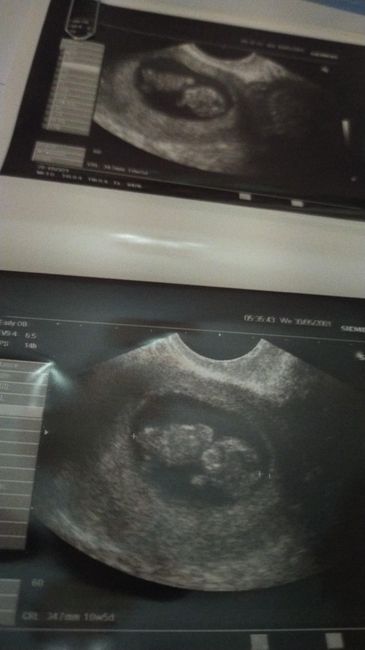

Ho caricato una foto nel post di Bolla

1680 giorni fa

Ragazze,secondo il metodo ramzi quale sarebbe il sesso? Ecografia interna😊 grazie a chi risponderà